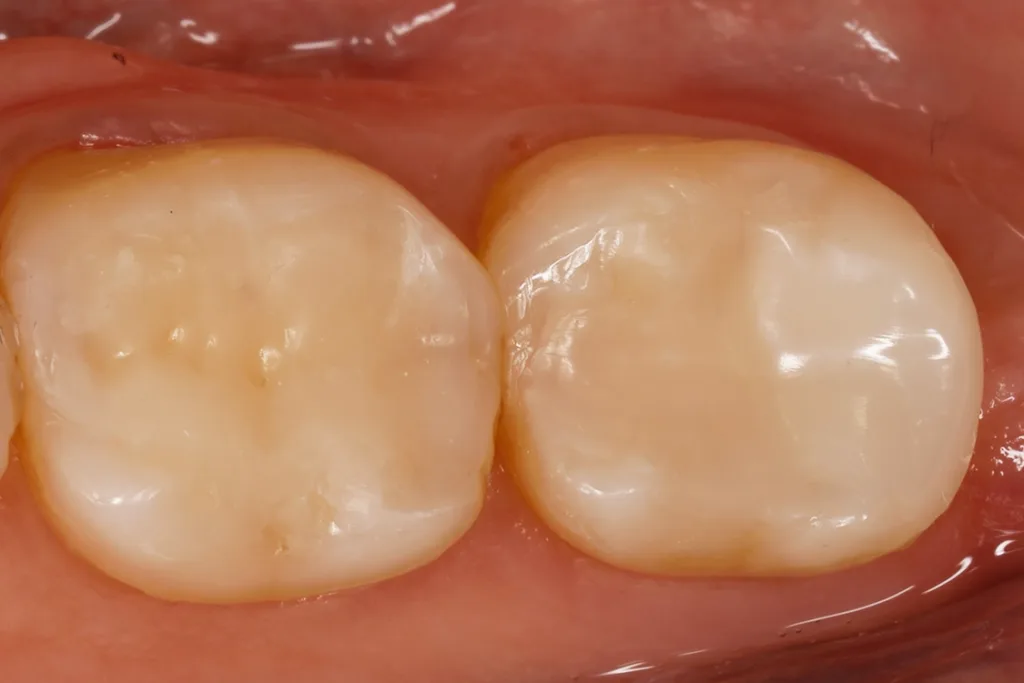

Fall 3: Austausch einer insuffizienten Amalgamfüllung an einem oberen ersten Molaren

Bei dem 75-jährigen Patienten fiel bei einer Routinekontrolle die randkariöse, insuffiziente Amalgamfüllung in Zahn 26 auf (Abb. 6). Nach FACE-unterstützter Exkavation zeigte sich ein zentral stark verfärbtes, aber hartes und nicht mehr auf Fluoreszenz ansprechendes Dentin ohne jegliche Pulpa-Expos (Abb. 7). Aufgrund der etwas eingeschränkten Compliance des Patienten erfolgte auch hier die Versorgung unter Kofferdam, da nur so eine ungewollte Zungenbewegung effektiv unterbunden werden konnte. Auch hier fiel die Wahl auf das Zwei-Schritt-Universaladhäsiv, welches wieder in der selektiven Schmelzätztechnik (37,5% Gel Etchant, Kerr, Orange, CA, USA) angewendet worden war. Die Abbildung 8 zeigt die ausgearbeitete und polierte Versorgung des Zahnes unter Einfassung des distopalatinalen Höckers. Als Farbe kam hier die A3 von GrandioSO Unlimited zur Anwendung. Das Material wurde in insgesamt drei Inkrementen eingebracht, modelliert und mit einem Hochleistungs-Lichtpolymerisationsgerät (Elipar Deep Cure, 1.500 mW/cm Solventum, Seefeld) polymerisiert. Die Ausmodellation des Höckers und des großen Kauflächenareals verlief aufgrund der sehr angenehmen Konsistenz des Materials problemlos. Sehr entgegen kam hier die lange Verarbeitungszeit des Kompositmaterials.